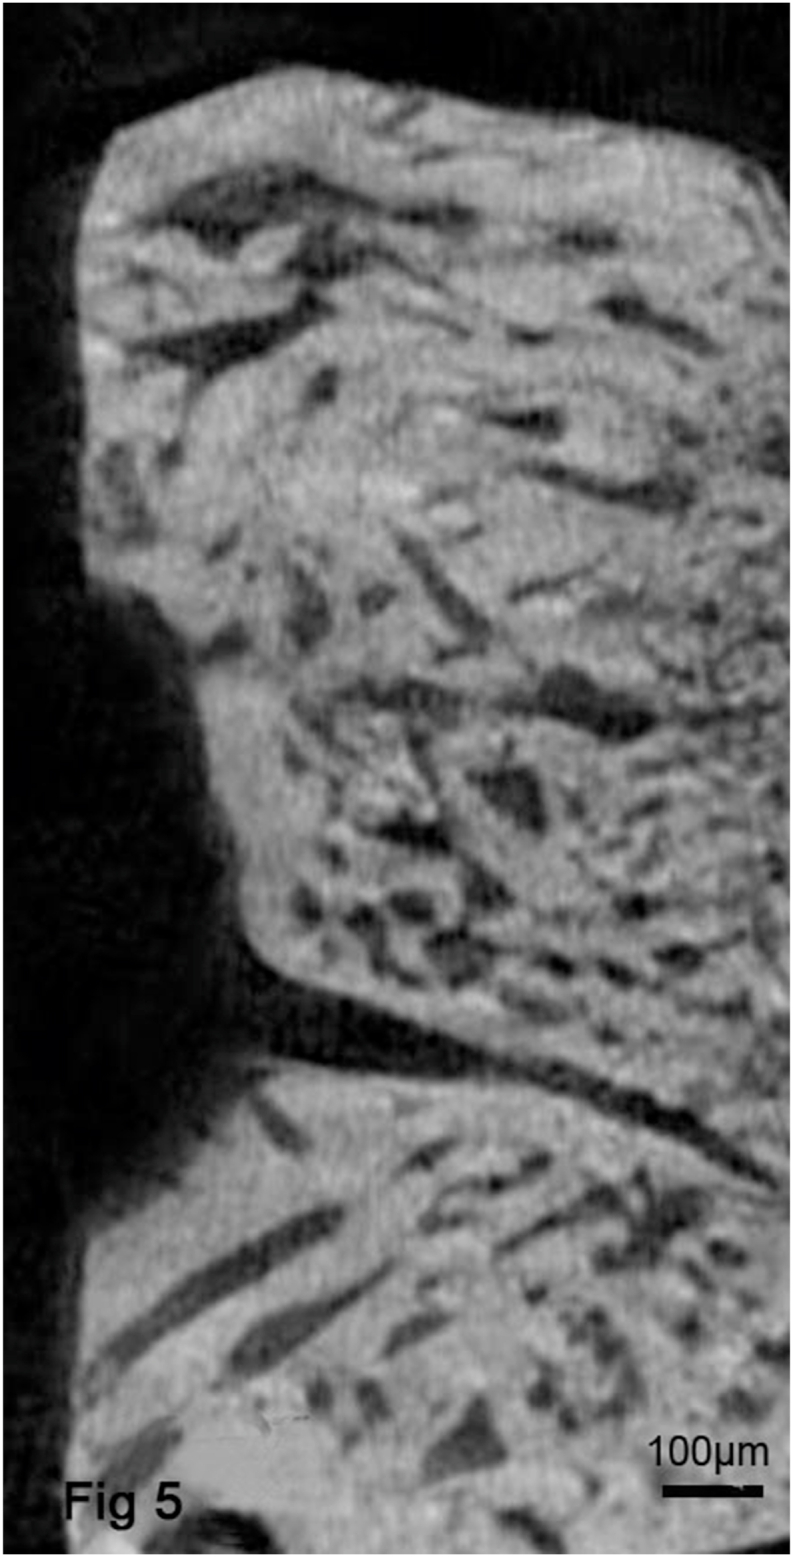

All experimental mandibles, including from the AZ31B and Collagen groups, showed the presence of an almost integrated cortical bone and a well-defined alveolar canal. A dense trabecular network was visible in all segments through high resolution micro-CT images in all groups. However, much thinner bone and less newly formed trabecular bone were found in the distracted callus from the Collagen group (Fig. 4) compared with the AZ31B group (Fig. 5). The structures treated with AZ31B magnesium alloy were similar to the adjacent bone, displaying a dense cortical bone-like structure peripherally and a large region of newly formed trabecular bone in between (Table 2). Tb.Th was significantly higher in the AZ31B (0.338 ± 0.08) and control groups (0.417 ± 0.05) than the Collagen (0.178 ± 0.04) group (P < 0.05). Tb.Sp was significantly lower in the Collagen group than the controls (P < 0.05). Higher Tb.N, BMD and Bv/Tv results were found in the AZ31B group than the Collagen group; however, these results were not significantly different.

Fig. 5.

Micro-CT images from the AZ31B group showed a rough and uneven bone surface and the thick trabecular bone similar to that of adjacent bone. From the analysis of these images, significantly higher Tb.Th, and lower Tb.Sp were obtained.